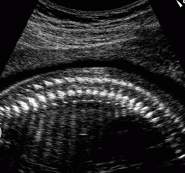

Yandaki görüntü size aşina geldi mi? Resimde bebeğin omurgaları net ve adeta teker teker sayılacak kadar belirgin bir şekilde gözleniyor.

Bu gebelik haftasında yapılan bir ultrason bebeğiniz ve diğer gebelik yapılarının

durumu hakkında oldukça ayrıntılı bilgiler verebilir.